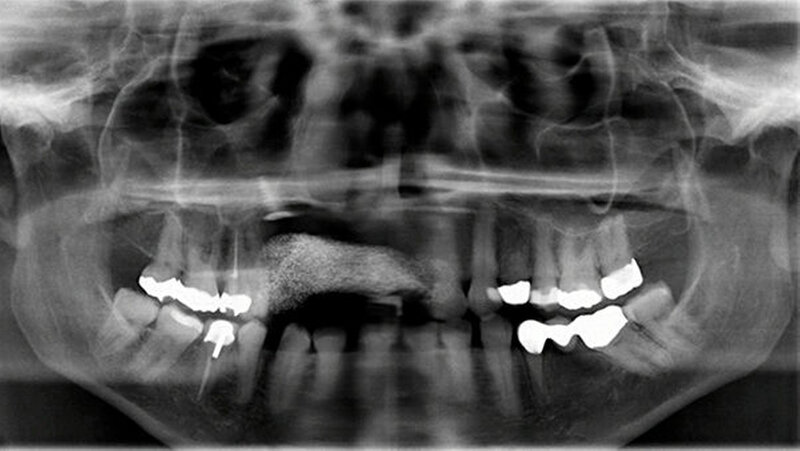

In der Panoramaschichtaufnahme zeigte sich eine Osteolyse im Bereich der Oberkieferfront Regio 12 (Abbildung 2), weshalb eine 3-D-Bildgebung zur Größenbestimmung durchgeführt wurde. Die durchgeführte CT-Diagnostik ergab den Nachweis eines Os librum mit den Maßen 7 x 8 x 11 mm unter Beteiligung der beiden Pfeilerzähne 11 und 13 (Abbildung 3).